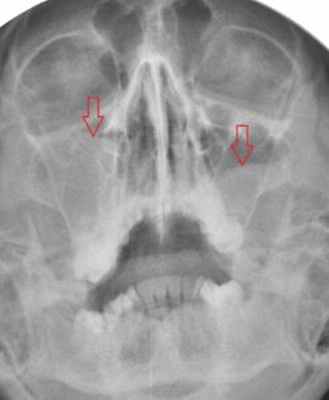

На рентгеновском снимке о наличии кисты можно говорить в случае, если в проекции пазухи имеется затемнение с краем, который может являться частью круга. Центр данного круга должен при этом находиться внутри пазухи, а не за ее пределами – в таких случаях речь идет, скорее, о наличии жидкости в пазухе (вязкого характера) или об ином экссудативном процессе. На рентгенограммах пазух кисты могут давать и картину тотального затемнения пазухи – в этом случае необходима дифференциальная диагностика с экссудативным гайморитом, муко- и пиоцеле, опухолью и т. д. На рентгенограмме определяются кисты верхнечелюстных пазух с обеих сторон. Обратите внимание на верхний край затемнения в пазухах – он ровный, имеет полукруглую форму, характерный для кист вид. В данном случае с целью уточнения размеров и локализации кист необходима компьютерная томография околоносовых пазух. Характерная для кисты верхнечелюстной пазухи картина при компьютерной томографии: обратите внимание на объемное образование в правой гайморовой пазухе, которое имеет ровные, закругленные края (отмечены стрелкой красного цвета), однородную структуру и плотность, соответствующую жидкости (+5…+15 единиц по шкале Хаунсфилда). Видно также, что выводной проток пазухи сужен, слизистая ячеек этмоидальной пазухи с правой стороны утолщена, имеет место утолщение слизистой носа – все это признаки катарального этмоидита, ринита, возникшего вследствие нарушения мукоцилиарного клиренса. Не путайте кисту верхнечелюстной пазухи с пролабирующим в полость пазухи корнем зуба (отмечен стрелкой) – на рентгенограммах очень часто тень зуба дает картину, имитирующую кистозное образование в пазухе – зачастую только с помощью КТ пазух можно различить эти два состояния. На данных изображениях также представлена киста гайморовой пазухи справа – обратите внимание на аксиальный срез (слева). Только по одному аксиальному срезу сложно сделать вывод о том, что за образование находится в полости пазухи, однако при выполнении реформаций в сагиттальной плоскости можно убедиться, что это именно киста большого размера (по характерному для кисты ровному закругленному краю, отмеченному стрелкой). Также на изображении справа видно, что слизистая оболочка гайморовой пазухи справа утолщена, а в ячейках решетчатой кости с этой же стороны визуализируется содержимое в большом количестве, выводные протоки гайморовой и этмоидальной пазух не прослеживаются. В данном случае наличие большой кисты в гайморовой пазухе спровоцировало развитие воспалительной реакции слизистой и явилось причиной правостороннего этмоидита. На изображениях можно проследить следующую патологию – часть этмоидальной пазухи пролабирует в полость носа (пролабирующая ячейка заполнена содержимым жидкостного – исходя из ее плотности – характера; отмечена стрелкой). Утолщена также слизистая верхнечелюстных пазух, резко сужены их выводные протоки (отмечены цифрой 1 на левом скане). На изображениях в аксиальной плоскости (слева), сагиттальной (в центре) и корональной (справа) плоскостях видна киста правой гайморовой пазухи. На КТ она выглядит как образование с ровными краями, жидкостной плотности (обозначена на всех сканах красными стрелками). На крайнем правом скане также цифрой 1 обозначена правая половина этмоидальной пазухи, заполненная содержимым. Имеются также признаки катарального гайморита (на левом скане) – оцените слизистую оболочку левой гайморовой пазухи – она явно утолщена. Небольшая киста гайморовой пазухи на КТ справа. Отмечена стрелками. Располагается пристеночно у задних отделов медиальной стенки и нижней стенки пазухи. Не вызывает нарушений отхождения слизистого секрета из пазухи.